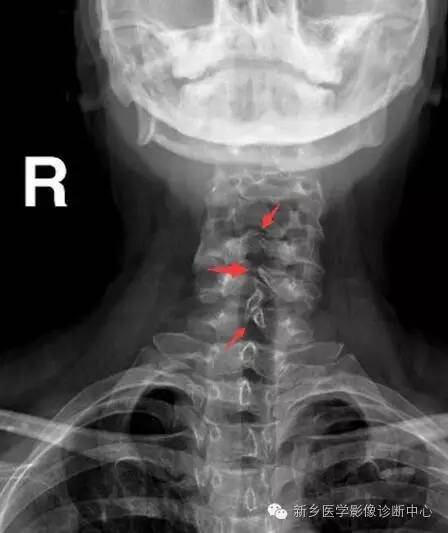

多发生于腰骶部,偶见于颈胸段。

X线:棘突、椎板缺损

(1)隐性脊柱裂:神经管几周围组织已闭合,椎弓存在裂隙,由纤维组织、软骨组织连接,无脊膜或神经组织膨出。